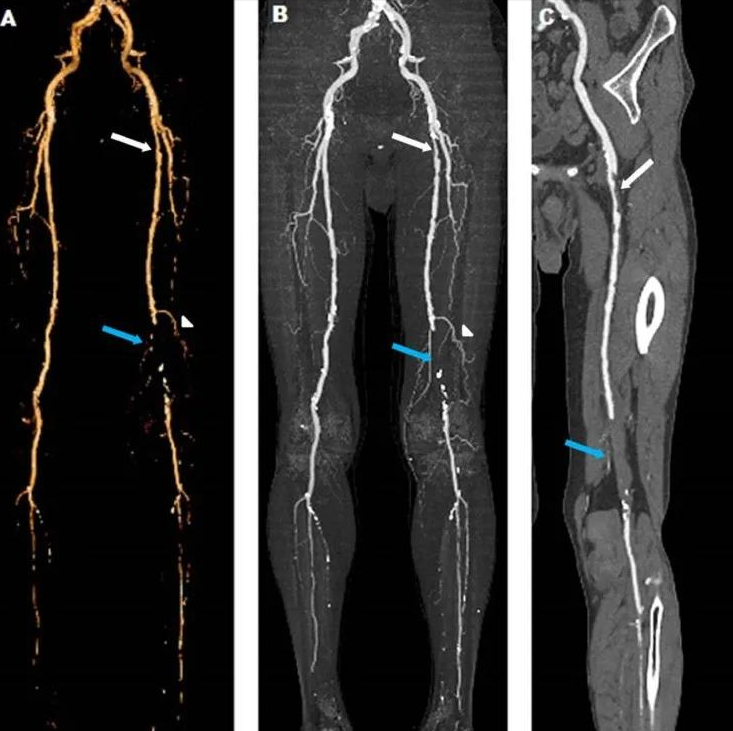

于是赶紧给老爷子进行了下肢血管的彩超检查 , 结果发现老爷子整个下肢血管已经不同程度地出现了闭塞 , 有一些血管已经闭塞到了90% , 有一些血管已经完全的闭塞了 。

针对这种情况进行腰部的治疗 , 没有效了 。 必须要进行血管外科的干预 , 所以赶紧联系了血管外科 , 建议老爷子住院治疗 , 否则有截肢的可能 。